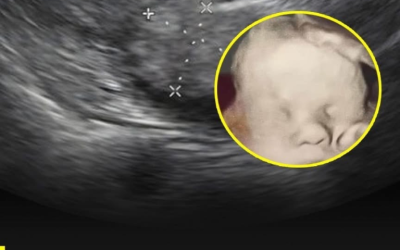

Gottes Hand im Ultraschall: Ein Moment, der die Welt bewegte

Medizinische Bilder zeigen meist nur das, was die Wissenschaft erklärt, aber manchmal gibt es auch Fotos, die viel tiefere Emotionen…